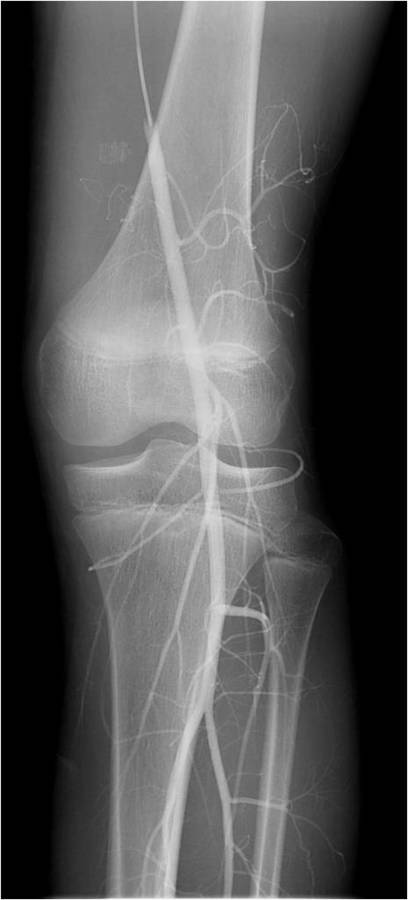

Gallery of Unlabled Radiographs from Lecture (Dr. French) - 2020

Click a thumbnail to enter the gallery display. Click the file name link at the bottom left of the gallery display to view the image at high resolution.

Labeled Plates from Lecture (Dr. French) - 2020

RadiologyLowerLimbThoraxQuestionPoolLabeled_01_2020.pdf

Click right side of plate to step forward or left side of plate to step backward.